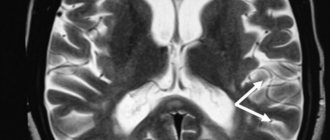

Cerebral gliosis: to worry about or not to worry about?

Magnetic resonance imaging is an informative non-invasive way to study cerebral structures. Diagnosis of pathological processes of the brain